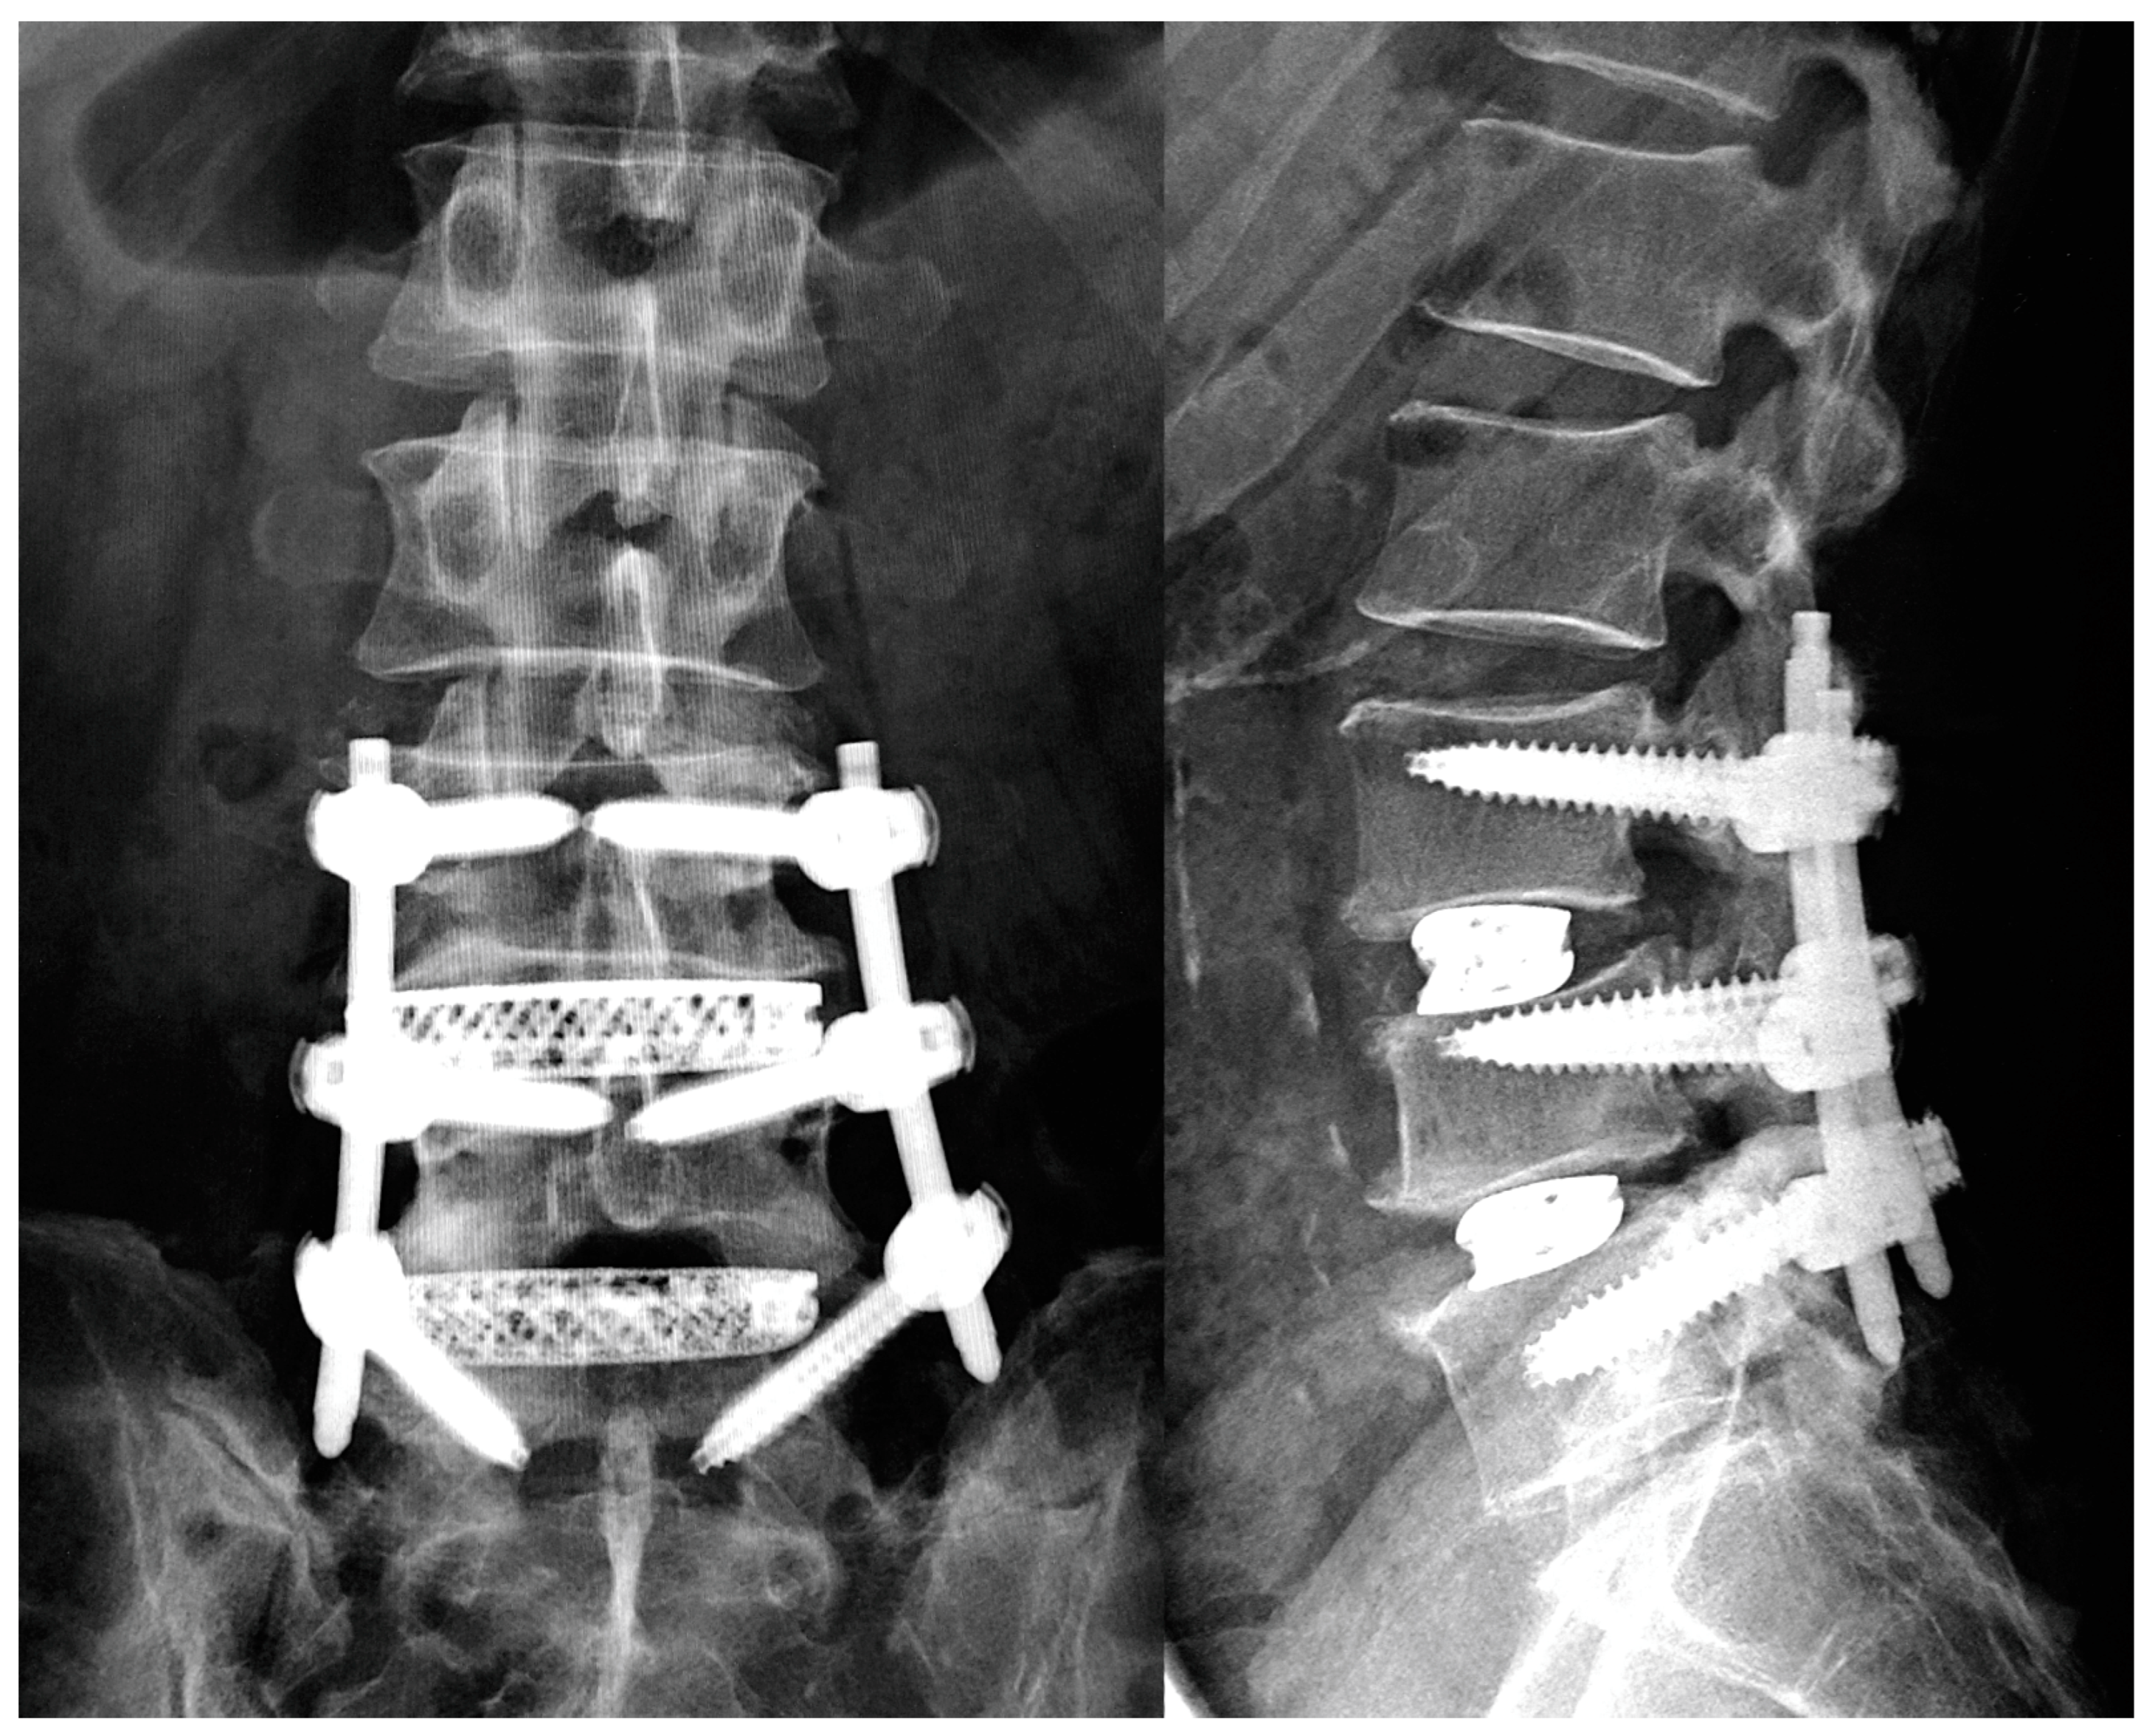

2.2. Surgical Procedure

2.4. Radiological Assessments